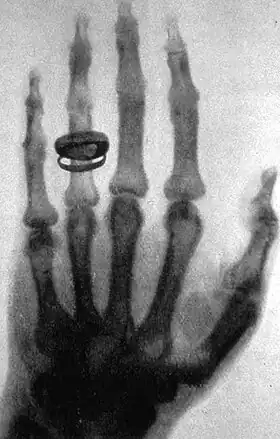

X-ray of a hand. X-rays are a common medical test.